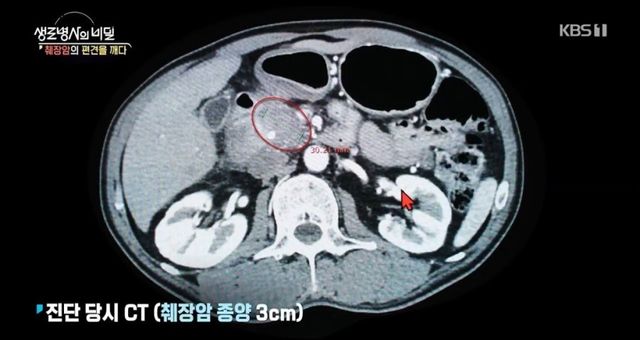

췌장암 3기 판정받은 사람이 느낀 증상

알았어도 이미 늦어서 정말 무섭습니다